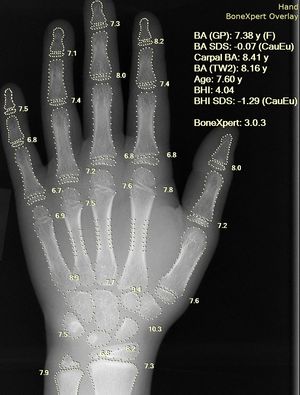

- 투사 방사선 촬영 (Projection Radiography): 흔히 엑스레이(X-ray)라고 불리는 이 기법은 X선을 인체에 투과시켜 영상을 얻는다. 접근성이 좋고 비용이 저렴하여 1차 검사로 많이 사용된다. 유방 촬영술과 DXA는 저에너지 투사 방사선 촬영을 이용한 검사이다.

유방 촬영술 및 DXA는 각각 유방암 및 골다공증 평가에 사용되는 저에너지 투사 방사선 촬영의 두 가지 응용 분야이다.